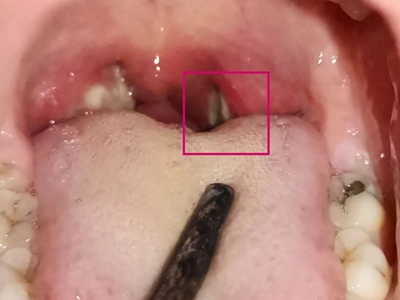

化脓性扁桃体炎单侧扁桃体变大化脓图

化脓性扁桃体炎咽部单侧扁桃体肿大突出,颜色呈鲜红色,形状不规则,黏膜表面凹凸不平,附有黄白色物质,伴有明显疼痛等自觉症状。